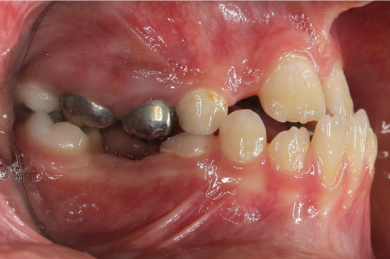

-  فک پایین جلو است یا فک بالا عقب است

- فک پایین عقب است یا فک بالا جلو است